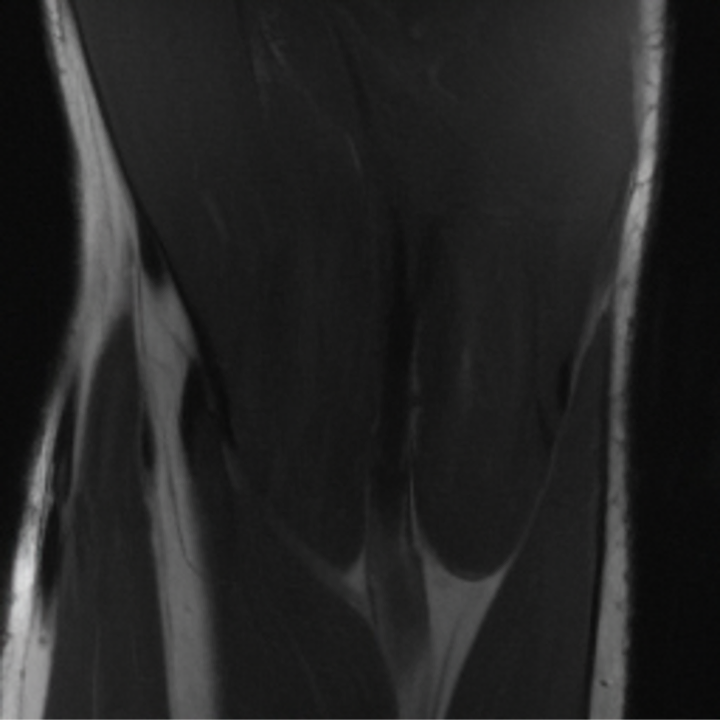

5.3 Out-of-Domain Generalisation

One way to test the generalization capability of the trained X-Diffusion is to test it on a completely different domain from an MRI dataset not seen during training. We report the single-slice results on NYU fastMRI [37, 82], a knee MRI dataset, using the X-Diffusion trained on the BRATS brain MRIs. The results are shown in Figure 9 and Table 2. It shows how successfully X-Diffusion is able to generate knee MRIs from a single image, despite not seeing knees at all in training. To qualitatively assess how realistic our generated 3D volumes were (produced from a single slice), we gave 20 generated examples alongside their real MRI counterparts to an expert orthopaedic surgeon. He was then asked to identify the real example from a given pair. The surgeon identified with certainty only 10 real knee MRIs out of 17, while could not decide on the remaining 3 of the 20 MRI pairs. This further validates the generated out-of-domain MRIs.